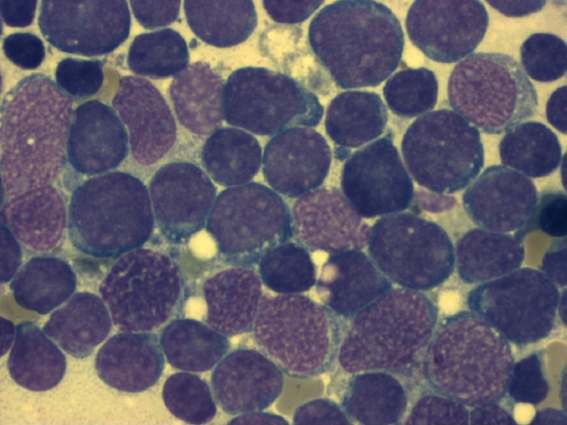

1906年6月7日

James Homer Wright报道了骨髓染色的方法,并描述了巨核细胞和血小板。

1957年9月12日

E. Donnall Thomas等报道了第一例人类的静脉骨髓移植。